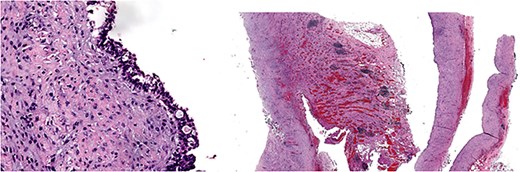

Give the symptomatology and anatomical impact, GDC resection was prioritized. Planned laparoscopic wedge resection was converted to upper midline laparotomy due to dense adhesions. The GDC, ~10 × 10 cm, originated from the posterior stomach wall with no luminal communication. The cyst ruptured during resection; the stomach wall was reinforced with sutures (Fig. 3). Histopathology confirmed GDC, showing gastric layers and underlying smooth muscle bundles, without atypia (Fig. 4). Post-operatively, the patient developed postprandial vomiting and abdominal pain and were attributed to small bowel adhesions, which resolved with conservative management. The patient achieved full recovery thereafter.

Histology image: Sections show a non-communicating cystic structure with a well-defined smooth muscle layer. No atypia or malignancy. The epithelium is flattened without atypia and occasional mucin-producing cells. Focal granulation tissue seen within smooth muscle bundles.